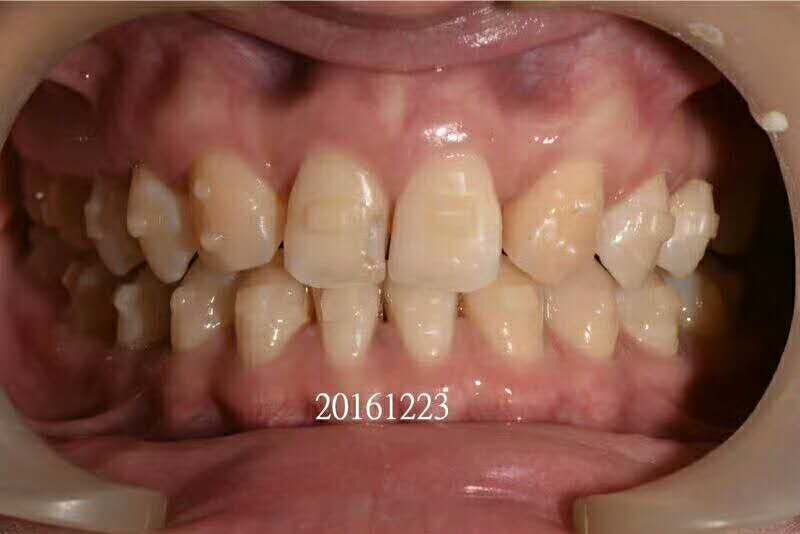

想要矫正牙齿,但又错过了最佳矫正时机,现在年龄大了,不知道现在矫正效果好不好,而且网上那么多人说成年人矫正这不好,那个要顾虑,更是不敢开始。今天小编就来跟你掰扯掰扯那些让你望而却步的“谣言”是不是真的。

青少年时期是牙齿矫正的黄金年龄,但是并不是说成年人就不能做了。只要牙周健康,多大年龄都可以做牙齿矫正,因为我们的牙齿终生都可以移动。虽然成年人颌骨改建以及牙齿移动速度较儿童慢,但由于成人合作程度高,治疗目标明确,受生长发育等不确定因素影响小,一样可以取得非常好的治疗效果。